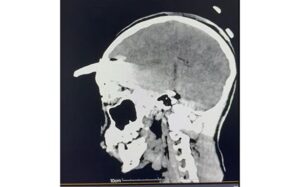

Tras confirmarse un traumatismo craneoencefálico severo, se realizaron estudios inmediatos que determinaron la profundidad y ubicación del objeto.

Los estudios de imagen permitieron ubicar con precisión el objeto, mientras que el menor recibía tratamiento con antibióticos de amplio espectro para prevenir infecciones asociadas con el instrumento metálico.

Después de un análisis minucioso y una planeación quirúrgica, el doctor Ornelas González dirigió un procedimiento de cuatro horas que permitió retirar exitosamente el machete curvo sin afectar tejido cerebral, en una intervención que confirmó la pericia y capacidad del equipo médico.